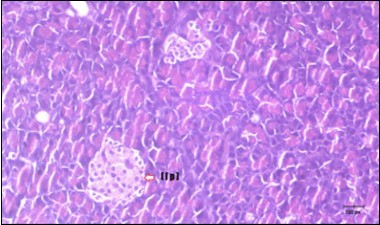

Histological examination of pancreas of the control rats showed normal sized islets of pancreas (Ip) compared to the diabetic rats which showed markedly atrophic islets of pancreas (I.p.) (Figure 8 and Figure 9). Pancreas of in groups (3) and (4) rats showed mild atrophic islets of pancreas (I.p.) with inflammatory cellular infiltrate (Figure 10 and Figure 11). The pancreas of rats in group (5) showed nearly normal islets of pancreas (I.p.) with few inflammatory cellular infiltrate (I.c.) (Figure 12).

Figure 11.Photomicrogragh of pancreas section of treated rat with Glimepiride showing mildly improved of isled of Langerhans with large number of cells (dashed-arrow). (H&E) (40X).

Photomicrogragh of pancreas section of treated rat with Glimepiride showing mildly improved of isled of Langerhans with large number of cells (dashed-arrow). (H&E) (40X).